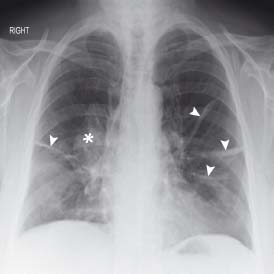

胸部レントゲンには肺や気道、血管など多彩な構造が映ります。その中で索条影は、紐のように細長く見える影を指します。

気管支や血管がかすかに映ったもの、あるいは過去の肺炎などにより線維化が生じた部分が原因になることがあります。

呼吸器内科では、肺全体の形態を見ながら索条影の位置や長さを確認し、病変の有無を判断します。

線状影は、索条影に似ていますがもう少し幅が細い場合が多く、放射線科では微妙な違いを区別します。

線状影は、瘢痕(傷跡)や微小な炎症が残った結果として現れることもあり、過去に結核や肺炎を経験した人の肺に見られる場合も珍しくありません。